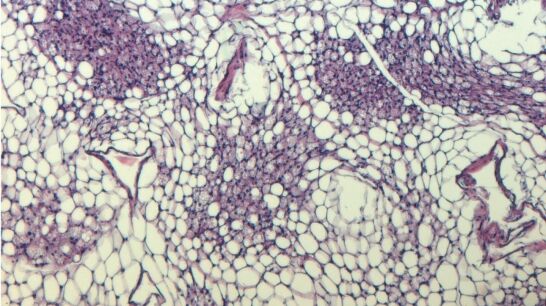

"Si un transportador de inosina es menos activo, los ratones se mantienen significativamente más delgados a pesar de una dieta alta en grasas", informa dicha agencia. Normalmente, las células grasas almacenan energía. Sin embargo, en las células de grasa marrón, la energía se disipa en forma de calor, por lo que la grasa marrón sirve de calentador biológico. Por ello, la mayoría de los mamíferos disponen de este mecanismo que en los humanos mantiene calientes a los recién nacidos; mientras que en los adultos, la activación de la grasa parda se correlaciona positivamente con la salud cardiometabólica.

Sin embargo, lo más interesante fue cómo las células de grasa parda intactas respondieron a la llamada de auxilio molecular: Se activaron por la inosina (o simplemente por las células moribundas de su entorno). Así, la inosina avivó el fuego en su interior. Las células de grasa blanca también se convirtieron en sus hermanas marrones. Los ratones alimentados con una dieta alta en energía y tratados al mismo tiempo con inosina se mantuvieron más delgados en comparación con los animales de control y quedaron protegidos de la diabetes.